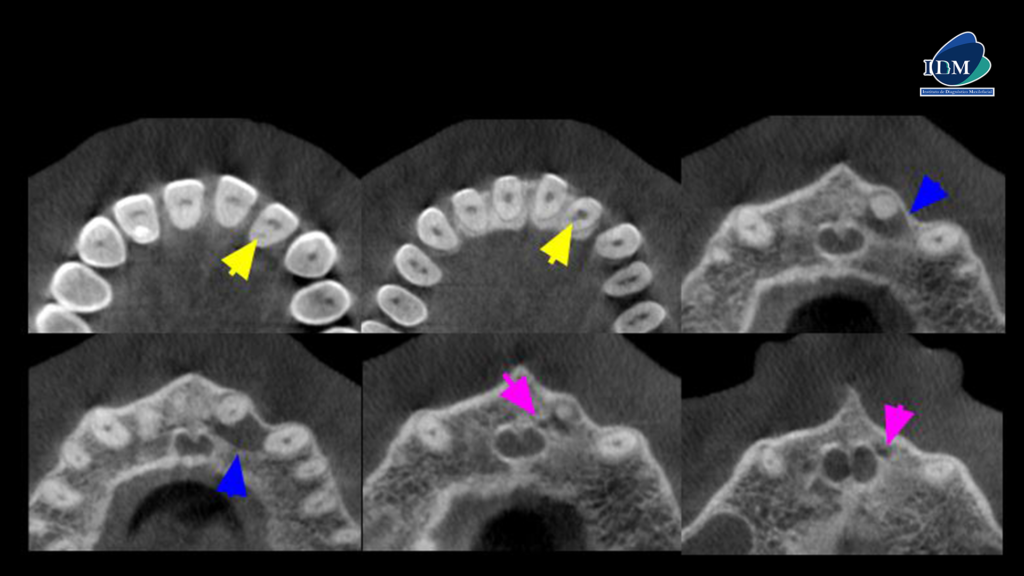

A la evaluación de la tomografía computarizada en los cortes axiales se observan tres hallazgos importantes; primero, la presencia de una imagen hipodensa puntiforme que nace desde el conducto pulpar hasta la cara palatina (flecha amarilla), un proceso osteolítico periapical de la pieza 22 (flecha azul) de forma redondeada que compromete la superficie mesial de la pieza 23 y ocasiona el adelgazamiento de la cortical vestibular, así como el aumento de la densidad ósea circundante compatible con quiste radicular y la presencia de un canalisis sinuosus que se extiende por palatino de la pieza 22 (flecha fucsia).

CORTES AXIALES